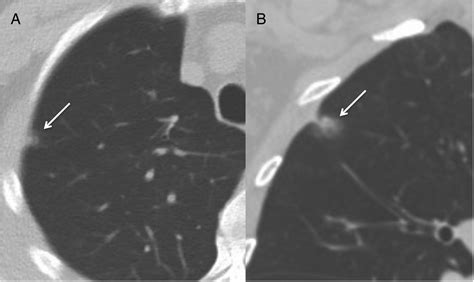

Pure Ground Glass Hazy, no solid component Serial CT scans over several years

Part-Solid Hazy with a dense solid center Requires closer follow-up and faster intervention